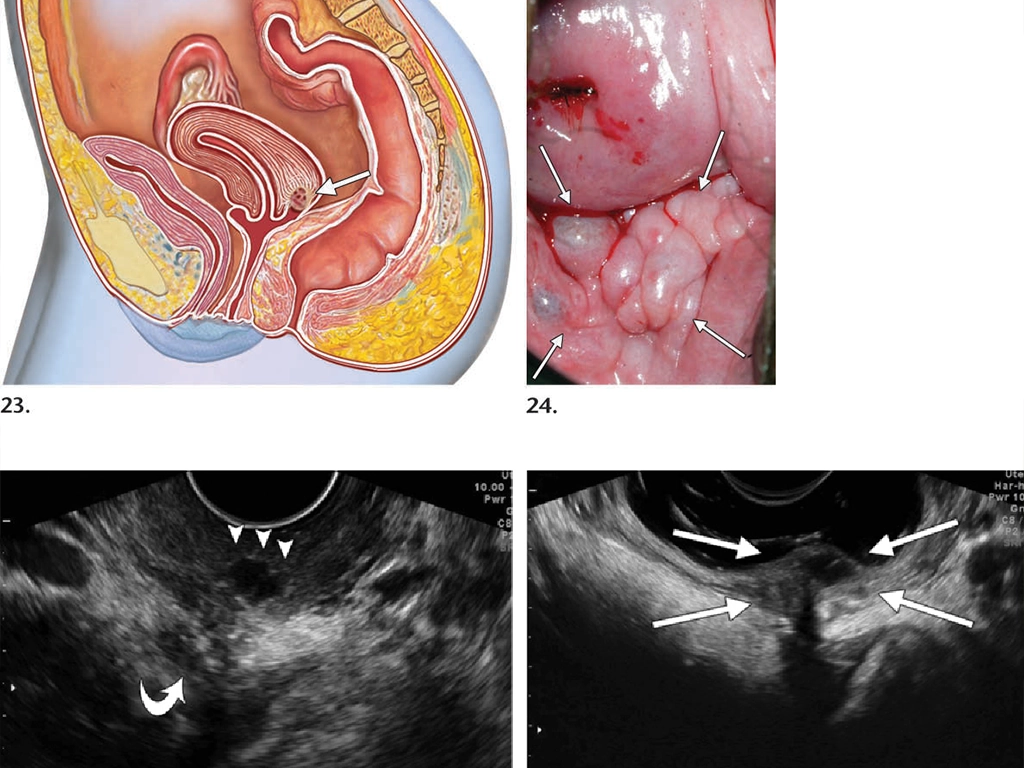

اندومتریوز یک بیماری التهابی estrogen-dependent است که با حضور بافت اندومتر در خارج از حفره رحمی مشخص میشود. این بیماری به سه شکل اصلی ظاهر میشود:

- اندومتریوز سطحی: ضایعاتی که روی صفاق لگن قرار دارند

- اندومتریوماس: کیستهای تخمدانی حاوی خون قدیمی

- اندومتریوز عمقی: ضایعاتی که به عمق بیش از ۵ میلیمتر در بافت نفوذ میکنند

کمپارتمان خلفی: درگیری رکتوم و روده

اندومتریوز کمپارتمان خلفی یکی از چالشبرانگیزترین انواع این بیماری است. سونوگرافی واژینال امکان بررسی دقیق سپتوم رکتوواژینال و دیواره قدامی رکتوم را فراهم میآورد.

نشانههای کلیدی:

- نشانه کلاه سرخپوستی (Indian Headdress Sign): retraction در دیواره قدامی رکتوم

- نشانه دنباله دار (Comet Sign): ضایعات با دنباله باریک

- ضایعات قارچی شکل (Mushroom-shaped lesions)

- کمپارتمانهای جانبی: اندومتریوما و چسبندگی

سونوگرافی ترانس واژینال در کمپارتمانهای جانبی به دنبال اندومتریوماها و چسبندگیهای آدنکسال میگردد.

ویژگیهای اندومتریوما:

- کیست یکلوکولر با اکوژنیسیته ground glass

- دیواره صاف و یکنواخت

- عدم وجود جریان آکوستیک